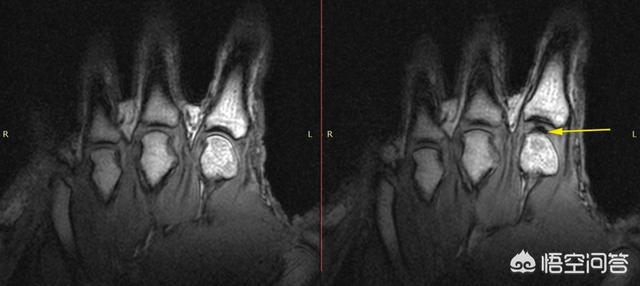

然而,2015年,阿尔伯塔大学的Greg Kawchuk和合作者使用核磁共振成像扫描仪记录了一名频繁出现关节病的志愿者的手指。在图像中,您可以看到指关节凸起部分突然出现裂痕。Kawchuk博士及其同事写道,这就是形成泡沫的结果,这种泡沫持续了一段时间,其创造可能是造成破裂噪音的原因。他们认为气泡在流体中产生了压力波,产生了声音。然而,目前还不清楚这一波如何能够强大到足以形成独特的裂缝。